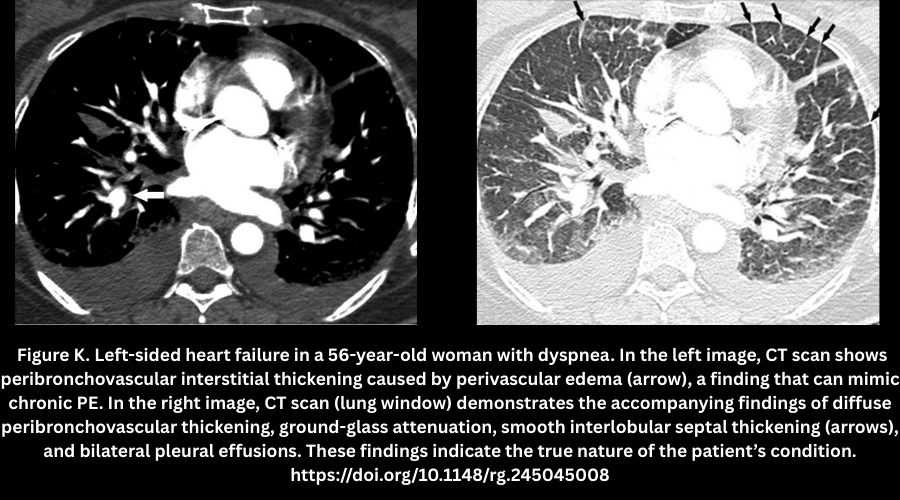

- Perivascular edema (Figure K).

- Seen in CHF; causes peri-bronchovascular thickening that resembles chronic PE.

- Accompanied by ground-glass opacities, septal thickening, and pleural effusions.